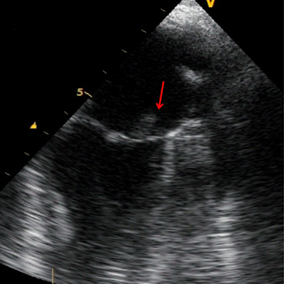

On the second day of her hospitalization, she had melena and gastroenterology adviced proton pump inhibitor. Her hemoglobin was 7.1 g/dL and 2 units of erythrocyte suspension were given. The patient had diffuse myalgia, palpitations and sinus tachycardia on electrocardiography. Her heart sounds were regular without murmur. During a physical examination, painless hemorrhagic cutaneous lesions were noted on her feet (Figure 1 [Fig. 1]). She was directed to cardiology and on echocardiography mild mitral regurgitation was noted. Transesophageal echocardiography (TEE) was planned in order to detect mitral regurgitation etiology. TEE showed mild mitral regurgitation and a vegetation on posterior mitral valve (Figure 2 [Fig. 2]). She was diagnosed with infective endocarditis and therapy was changed. Gentamicin (2x80 mg) plus ampicillin (4x3 gr) was started. On follow-up the patient still had fever, myalgia and discomfort. Two blood cultures revealed gram positive bacteria resistant to methicillin and the bacteria was identified as Staphylococcus aureus with BD Phoenix Automated Microbiology System. Also fluid sample (the fluid sample taken from her ankle) culture done in sheep blood agar revealed gram positive bacteria resistant to methicillin and the bacteria was identified as Staphylococcus aureus with BD Phoenix Automated Microbiology System. Both of the cultures’ isolates were resistant to methicillin and sefoxitine and susceptible to vancomycin, linezolid and teicoplanin. Although gentamicin plus vancomycin therapy was planned for the patient, vancomycin was not available so her therapy was changed to gentamicin (2x80 mg) plus linezolid (2x600 mg) according to culture antibiogram. The patient began to improve after medical therapy with linezolid and gentamicin. She had no fever anymore and her hemoglobin level was 9 g/dL. Blood urea and creatinine were in normal ranges 30 and 1 g/dL, respectively. In the third day her CRP-level began to decrease (20.1 mg/dL). Her CRP course was 12.6 mg/dL in the first week, 5.8 mg/dL in the second week, 3.2 mg/dL in the fourth week and 0.5 mg/dL in the sixth week. Control TEE showed mild to moderate mitral regurgitation and vegetation (Figure 3 [Fig. 3], Figure 4 [Fig. 4]). After six weeks of antibiotherapy (six week linezolid and two week gentamicin) she was free of infection and a control transthoracic echocardiography showed no mitral regurgitation or vegetation.

Figure 2: Vegetation on posterior mitral valve

Figure 3: Vegetation on posterior mitral valve (control)